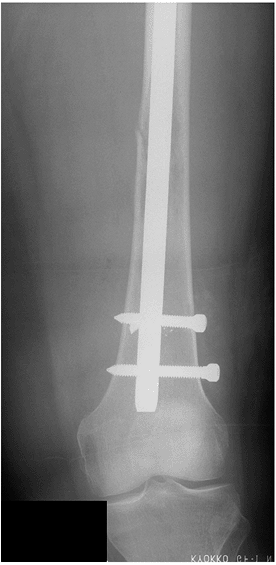

Figure 4.5-7

A distal diaphyseal pathologic femur fracture secondary to metastatic

disease was stabilized with a proximally and distally locked

cephalomedullary nail. -